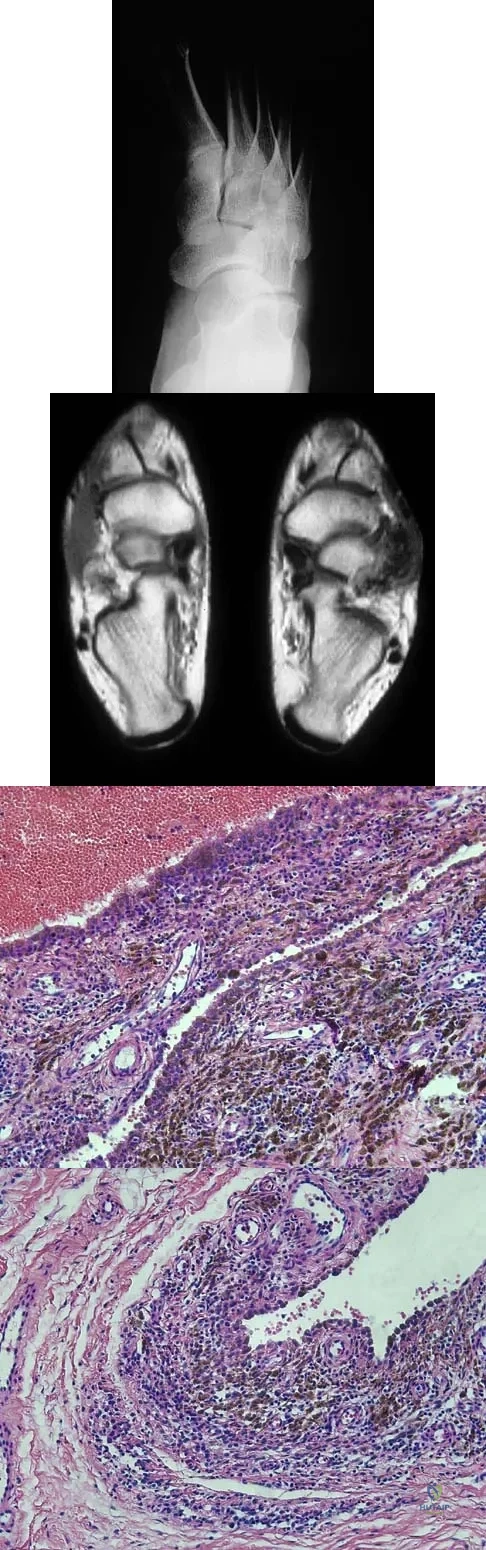

Question 100

A 16-year-old girl has a painful foot mass. A radiograph, MRI scan, and biopsy specimens are shown in Figures 35a through 35d. What is the most likely diagnosis?

Explanation